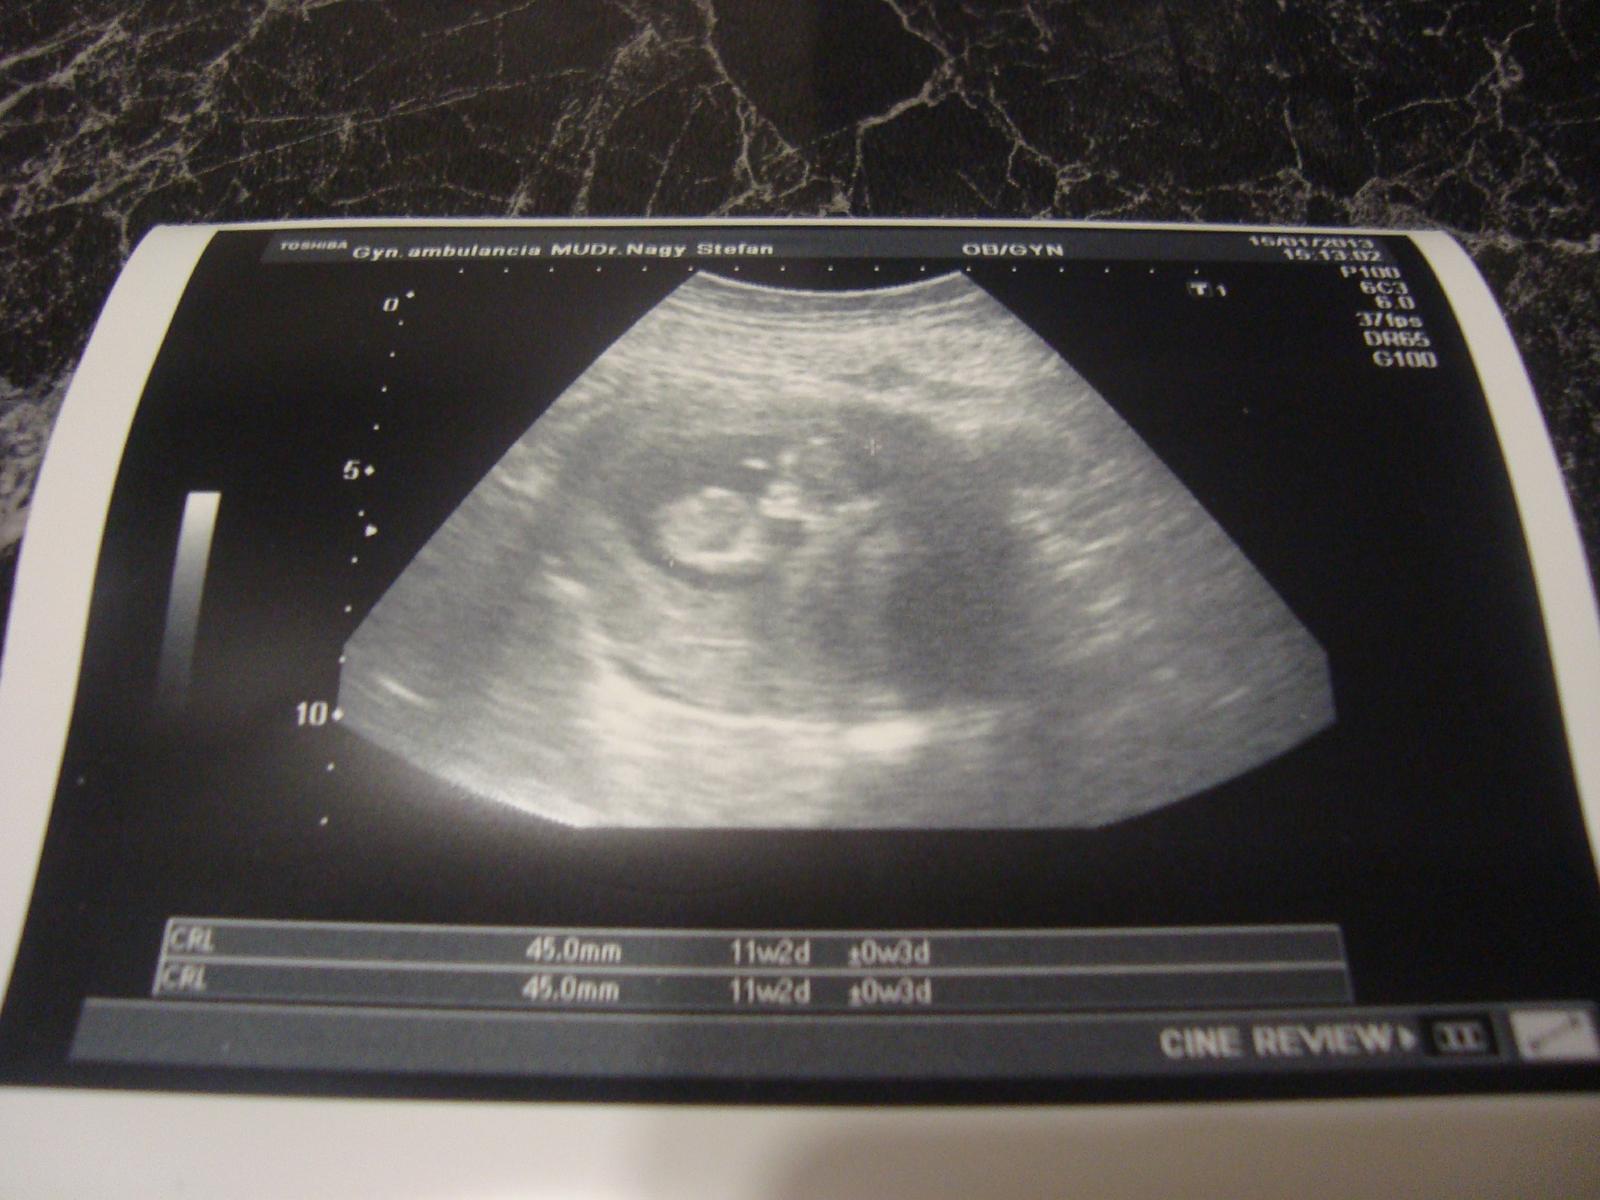

prvé sono za sebou, konečne som videla svojho drobčeka.bolo to krásne a dojemné.som šťastná že je všetko v poriadnu.meriame už 5,9 cm 🙂

Jéj už mám foto🙂

dakujem vam krasne vsetkym za vase pozitivne myslienky!!! uz som doma a poviem vam, ze dnesny usg by som dopriala uprimne zo srdca kazdej z vas. plodik maval rucickami a kopal nozickami jak nenormalny 😀. som sa smiala, ze zdravi mamku aj pana doktora a krici, ze ako mu je fajne v tom "bazene". prikladam fotku, nech vas potesi. vsetko som mala ok az na zvyseny tlak. ale mozno len zo vzrusenia, takze si ho budem teraz pravidelne doma merat a uvidime, ci bude lespi, ako u doktora.

@marin.frist dakujem krasne, ta fotka velmi nevystihuje ten realny pohlad na monitor, ten bol tisickrat krajsi 🙂

@cora41 dakujem! to bola iba normalna kontrola u mojho gyndosa. myom mi nerastie a uz je mensi ako plodik, takze uz to zacina byt menej nebezpecne pre babo. podla menstruacie som 11+1, podla usg ma babo 4,5 cm, co zodpoveda 11+2, cize 1 den rozdiel. ale nezlakni sa, lebo ja mam 178 cm a moj drahy 205 cm, takze my stale budeme mat velky rozmer.